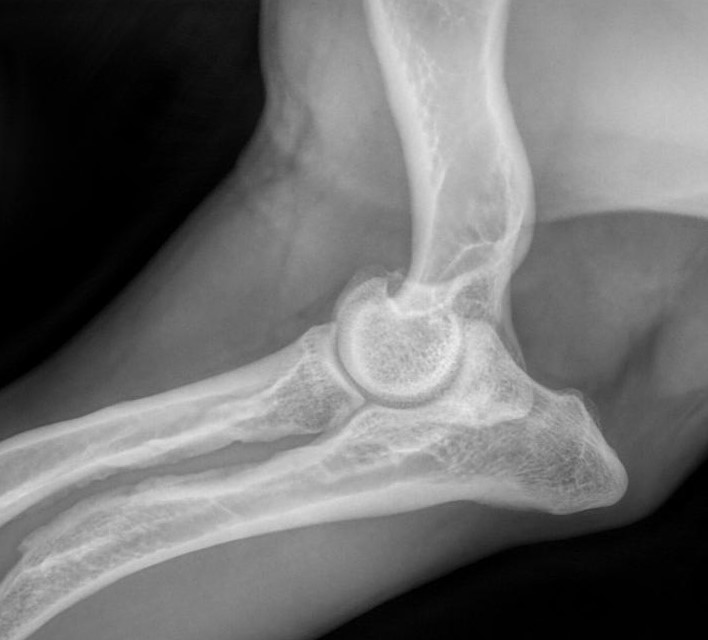

Kyynärnivelen inkongruenssi

Kondrodystrofisilla koiraroduilla on perinnöllinen luiden kasvuhäiriö, joka aiheuttaa jalkojen luiden pituuskasvun häiriintymisen jo sikiöaikana.

Kaikissa kyynärnivelen kasvuhäiriöissä oireet alkavat keskimäärin 4-7 kuukauden iässä. Tyypillinen oire on ontuminen, joka voi pahentua rasituksessa tai olla voimakkainta levon jälkeen. Ontuminen voi olla jatkuvaa tai ajoittaista. Omistajan voi olla vaikea havaita koiran ontumista, jos kasvuhäiriö on molemminpuolinen. Toisinaan kasvuhäiriö on molemmissa kyynärnivelissä, vaikka koira ontuu vain toista jalkaa. Usein oireet huomataan vasta aikuisiällä ja silloin oireet johtuvat kasvuhäiriön seurauksena kehittyneestä nivelrikosta.

Luiden pituuskasvu tapahtuu rustoisten kasvulevyjen kohdalla. Pituuskasvu loppuu, kun kasvulevyt ovat luutuneet kiinni. Kaikilla kondrodystrofisten rotujen koirilla raajojen luut ovat lyhyemmät ja paksummat ja myös normaalia käyremmät, mutta toisinaan kyynärluun kasvulinja sulkeutuu liian aikaisin ja värttinäluun jatkaessa kasvuaan luiden mittasuhteet muuttuvat epänormaaleiksi. Seurauksena voi olla kyynärluun epäyhdenmukaisuus (inkongruenssi), kun "liian pitkä" värttinäluu muodostaa portaan nivelpintaan tai värttinäluusta tulee liioitellun käyrä. Joskus värttinäluun yläpää menee osittain sijoiltaan. Joillain koirilla häiriö näkyy tassujen kiertymisenä ulospäin ja ranteiden taipumisena sisäänpäin. Kondrodystrofisilla roduilla taipumus kasvulinjan liian aikaiseen sulkeutumiseen on perinnöllinen ja siksi sitä voidaan vastustaa jalostusvalinnoilla.

Kyynärnivelen epäyhdenmukaisuus näkyy parhaiten röntgenkuvassa, jossa niveltä ei ole taivutettu (avautumiskulma 90 astetta tai enemmän). Röntgenkuvassa täytyy näkyä kyynärnivelen lisäksi koko kyynärvarsi. Epäyhdenmukaisuus (inkongruenssi) arvioidaan asteikolla INC0 – INC3, jossa INC 0 on yhdenmukainen ja INC3 on voimakkaasti epäyhdenmukainen nivel. Kondrodystrofisilla roduilla INC1 on vielä "normaali", mutta INC2- ja INC3-kyynärnivelet ovat selvästi epänormaaleja.

Arvosteluasteikko:

Kuvattaessa koiran on oltava iältään vähintään 12 kk

INC0 (normaali): Nivelrako on kapea ja tasainen, kyynär- ja värttinäluun välillä ei ole porrasta. Ei nivelrikkoon viittaavia muutoksia.

INC1 (lievä): Nivelrako ei ole täysin kapea ja tasainen: kyynär- ja värttinäluun välillä on pieni porras tai nivelraossa olka- ja kyynärluun välillä on korkeintaan 2 mm leveä rako. Ei nivelrikkoon viittaavia muutoksia.

INC2 (kohtalainen): Nivelrako ei ole kapea ja tasainen: kyynär- ja värttinäluun välillä on porras tai nivelraossa (incisura trochlearis) olka- ja kyynärluun välillä on 2–3 mm leveä rako.

INC3 (vaikea): Nivelraossa olka- ja kyynärluun välillä 3 mm tai sitä leveämpi rako tai kyynär- ja värttinäluun välillä on porras, tai nivel on muuten selvästi epämuotoinen.